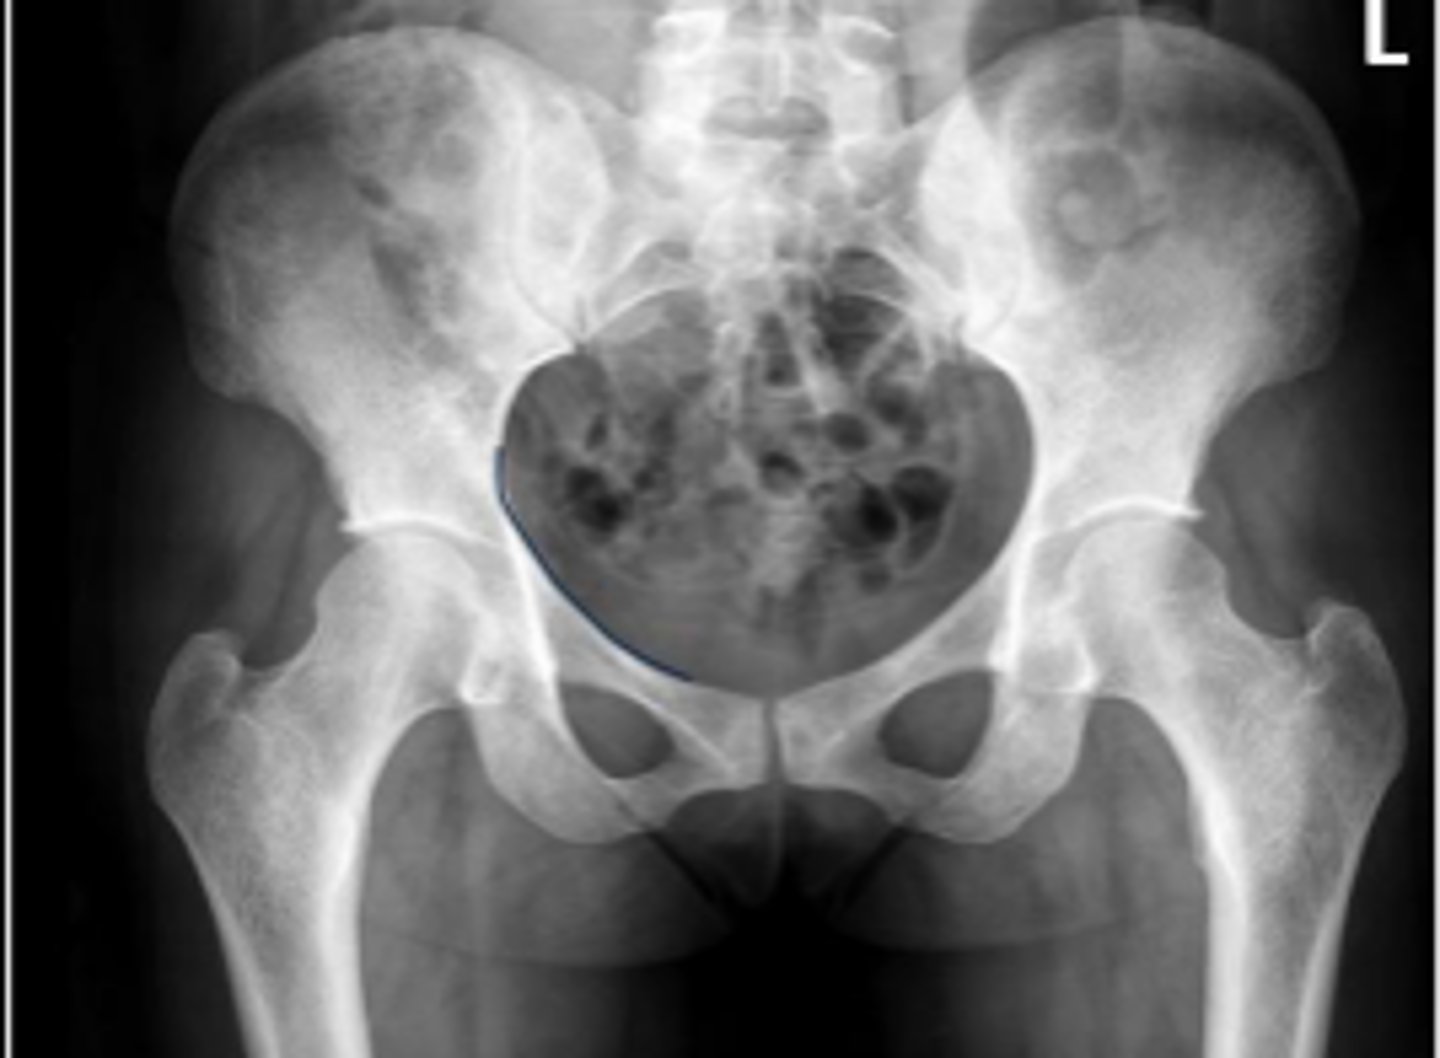

AP pelvis or bilateral hips

What is the name of the radiographic view?

10-15 degrees

How many degrees of internal rotation of the lower extremities is required for this view?

Iliac crest

What are the arrows pointing to?

Sacrum

What is the anatomical structure in between the lines?

ASIS

Left ischial spine

Sigmoid colon

What is outlined?

Right sacroiliac joint

What joint space are the arrows pointing to?

Pubic symphysis

What joint space is the arrow pointing to?